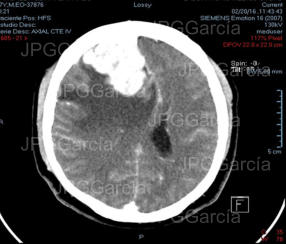

Tumor del plano esfenoidal clasificado por imagen como Meningioma visto a través de resonancia magnética cortes axial y coronal